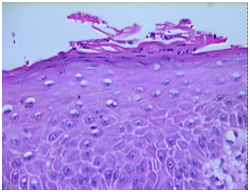

Figure 5 Fungal spores and pseuodohyphae invading the squamous epithelium- oral cavity.

Figure 6 Candidial hyphae with spores dispersed with the stratum corneum.

Chronic candidiasis: Prominent hyperkeratosis, pseudo-epitheliomatous hyperplasia, compressed orthokeratosis and a scaly encrustation may appear.5,6 Fungal spores and hyphae may be delineated in the absence of a Periodic acid Schiff (PAS) stain. Granulomatous dermatitis may also emerge with indeterminate granulomas comprising of lymphocytes, plasma cells, epitheloid cells and sporadic giant cells.5,6